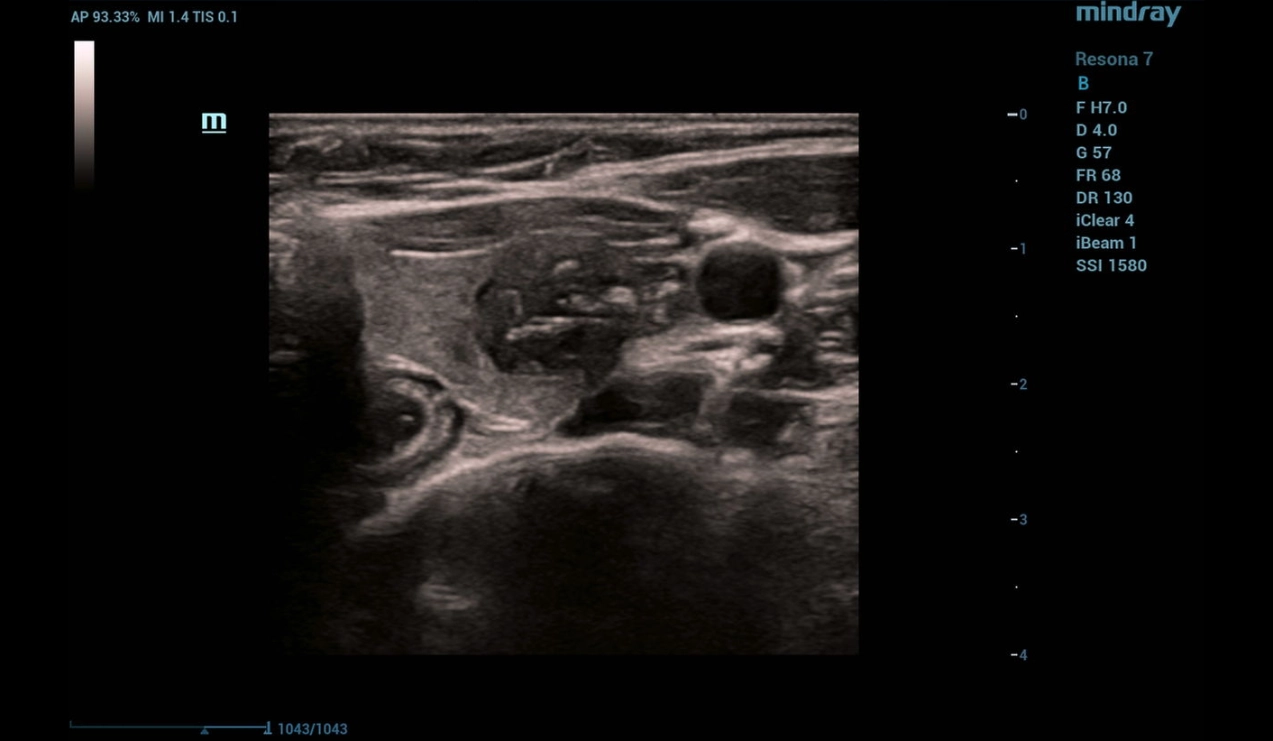

B-mode and Color Flow Doppler (CFD)

Ultrasonography was performed on a Resona 7 ultrasound machine (Mindray, China) using a linear probe L14-5WU. A cystic focal mass of anechogenic structure measuring 24x28x38 mm with smooth clear contours was detected in the left lobe of the thyroid gland (Fig. 1, 2)

throid-sclerotherapy-fig1-pc

Figure 1. B-mode image of the thyroid

Multiparametric ultrasound examination of the thyroid revealed a cystic focal mass in the left lobe without signs of malignancy.